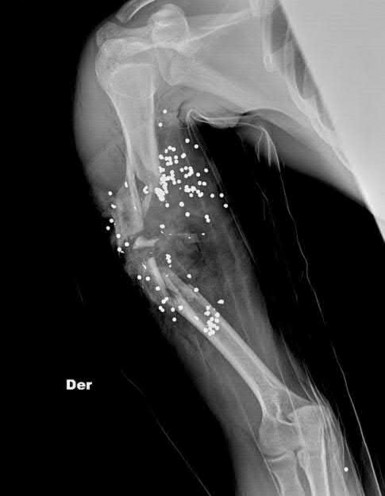

Figure A shows a radiograph of a 19-year-old male with an isolated shotgun injury. On physical examination, he has a 3 cm wound over the posterolateral aspect of his arm. In addition, he has weakness with wrist and finger extension, but no sensory deficits. The patient has received tetanus prophylaxis and antibiotics in the emergency department. What would be the next best steps in treatment?

This patient has sustained a shotgun blast to the midshaft humerus. The next best step would be irrigation and debridement, and external fixation of the fracture.

Shotgun injuries are typically treated as open fractures, whereas low-energy gunshot wounds are treated as closed fractures. The initial operative treatment of shotgun wounds should include irrigation and debridement and stabilization with external fixation. The goal of treatment is to stabilize the severe soft-tissue injury and bone loss, as well as to aggressively debride devitalized tissue and gross contamination.

Figure A shows a high velocity shotgun fracture to the left humerus with retained buck fragments. Illustration A shows a similar injury stabilized with external fixation.